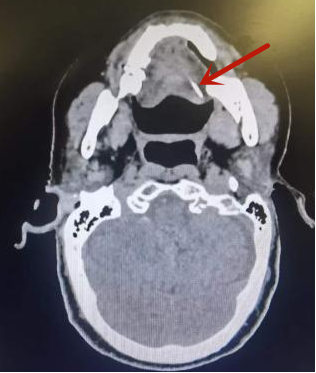

患者影像,箭头处为左侧舌根侧缘

刘阿姨高血压、糖尿病等老毛病控制的并不好,医生需要在确保全麻安全的情况下,尽快取出异物。经过耳鼻咽喉头颈外科主任叶京英、副主任尹国平等多位咽喉专家的讨论,在影像科的帮助下,通过特殊舌位定位方式顺利完成最新定位CT,证实了长条状异物斜横在左侧舌根侧缘至舌体中部,左侧舌根处异物尖端距离舌表面较浅。为避免异物再次移位,综合影像资料,手术团队快速制订方案。“首先找到离黏膜侧较近的异物端,小心切开黏膜,逐层分离,以取出异物,避免损伤口底、舌体内重要神经、血管。”尹国平说道。